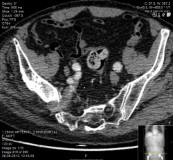

CT angiography (Figure 3) of the lower limb confirmed the aneurysmal origin of the sciatic nerve compression lesion with origin on the right internal iliac artery. It was completely occluded with a thrombosed aneurysm with approximately 4x5cm.

Figure 3 CT- angiography showing right internal iliac artery aneurysm.